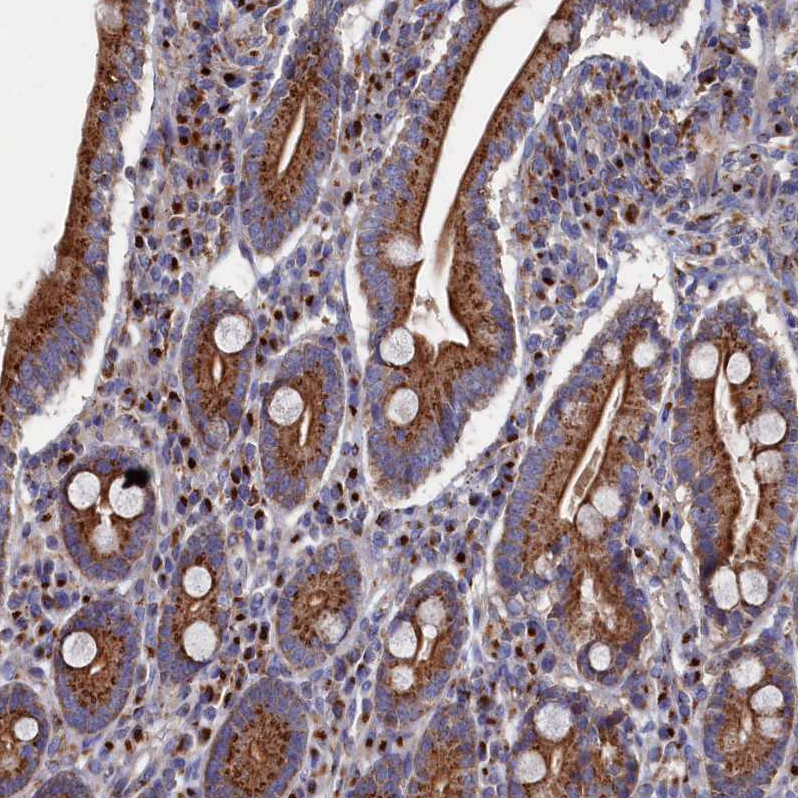

Immunohistochemical staining of human pancreas shows strong cytoplasmic granular positivity in exocrine glandular cells.